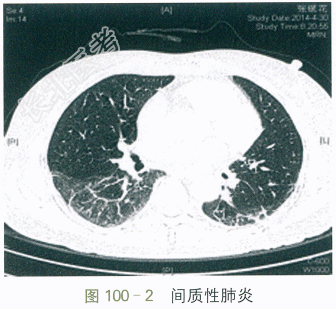

- [材料题] 患者,女性,59岁。因“口干眼干5年,伴胸闷气促2个月”入院。患者5年前起出现口干,进食干性食物时需饮水方可咽下,伴有双眼干涩、泪少,未予特别重视,3年前出现牙齿逐渐变黑,继而小片状脱落(见图100-1)。2个月前出现咳嗽、咳白痰,至当地医院治疗后一过性好转,但不久即出现活动后胸闷气促,上两层楼即感明显胸闷气促、呼吸困难,休息后稍好转,同时伴四肢及双手掌指关节酸痛。近日胸闷气促加重,休息状态下亦感胸闷。病程中无头晕头痛、无畏寒发热、无雷诺现象、无皮疹及光敏、无关节晨僵、无反复腮腺肿大。患者神志清,精神可,食纳夜眠可,二便正常,体重无明显减轻。高血压史14年,自服珍菊降压片1片bid,平素血压控制在120mmHg/80mmHg左右。否认糖尿病,冠心病史。否认病毒性肝炎及结核病史。否认药物过敏史。体格检查:T37℃,P76次/min,R18次/min,BP120mmHg/80mmHg。全身浅表淋巴结未及肿大,无皮疹及皮下结节。口腔可见多发龋齿,舌面光滑。两下肺可及Velcro啰音,心界不大,各心脏瓣膜区未及杂音。腹平软,肝脾肋下未及,双下肢无水肿。四肢各关节未及肿胀,压痛(-)。自身抗体:抗核抗体1:320,抗SSA抗体阳性,抗SSB抗体阳性,抗线粒体抗体阳性,抗ds-DNA抗体15.4IU/ml,抗核小体抗体2.0RU/ml。免疫球蛋白:IgG20.29g/L,IgA4.66g/L,IgM1.13g/L,IgE211.0IU/ml。血常规:RBC 4.75×10¹²/L,Hb 130g/L,WBC 7.06×10⁹/L,PLT 298×10⁹/L;ESR51mm/h;hs-CRP7.6mg/L。补体:C31.33g/L,C40.23g/L。血气分析:pH7.45,PaCO₂38.0mmHg,PaO₂65.0mmHg,SaO₂93.0%;乙肝免疫标志物、丙肝抗体、HIV抗体全阴性。肺HRCT:两肺间质性炎症(见图100-2)。腹部B超:肝脂肪浸润。心超:未见异常。肺功能:中度限制性通气功能障碍。